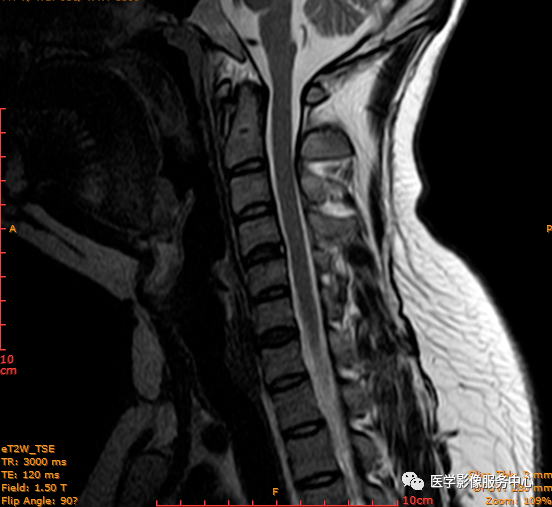

此病例为C4-5椎间盘后缘HIZ,工作中颈椎椎间盘HIZ发生率不高

图为C4-5、C5-6椎间盘后缘HIZ;